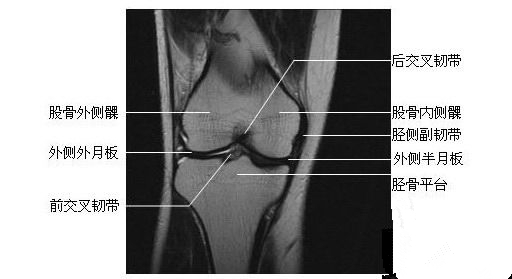

膝关节冠状面(四)

膝关节冠状面(五)